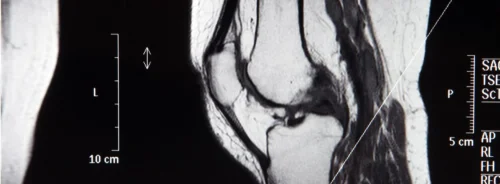

The multimodal model was trained using retrospective data from twelve clinical centres, incorporating T2-weighted, diffusion-weighted imaging and apparent diffusion coefficient sequences. It combined radiomic features, which quantify shape and texture, with clinical variables such as age, PSA levels, lesion location and PI-RADS scores. Radiomic extraction covered the entire prostate gland using segmentation masks generated by a deep learning model. Performance was assessed through retrospective and prospective datasets, ensuring temporal generalisability and robustness across scanner vendors and field strengths.

Sensitivity analysis demonstrated that performance depended heavily on the diversity of training data. Models trained on single-vendor datasets showed reduced generalisability, underscoring the importance of multicentric training. Scanner vendor and the presence or absence of an endorectal coil were considered in model variants, confirming the added value of multimodal training. Sequence-specific performance highlighted the superiority of biparametric MRI combinations over individual sequences alone.